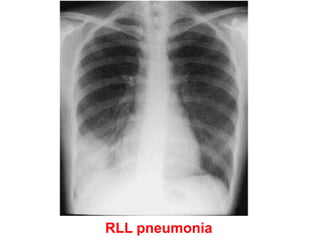

RLL pneumonia

• Chest X-ray showing a right

basal pneumonia in a previously

fit 40-year-old man with fever,

breathlessness, central cyanosis

and pleuritic pain. Chest signs

included bronchial breathing and

a pleural rub in the right lower

zone. The cyanosis was due to

the shunting of deoxygenated

blood through the consolidated

lung, the increased respiratory

rate leading to a low PaCO2

because of increased clearance

of carbon dioxide by the

unaffected alveoli. Streptococcus

pneumoniae was grown on blood

cultures.